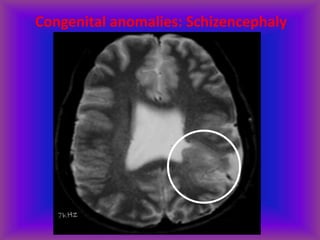

Congenital anomalies: Schizencephaly